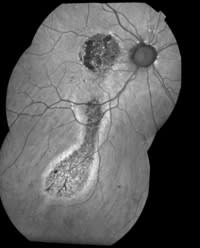

60-year-old female with chronic central serous chorioretinopathy

A composite autofluorescence image of the same patient clearly shows inferior tracts caused by the chronic leakage (drip) of the foveal CSC. The autofluorescence images were taken with a modified Topcon 50ex camera. PHOTOGRAPHS: MIKE RIFF, VITREOUS-RETINA-MACULA CONSULTANTS, NEW YORK, N.Y. |